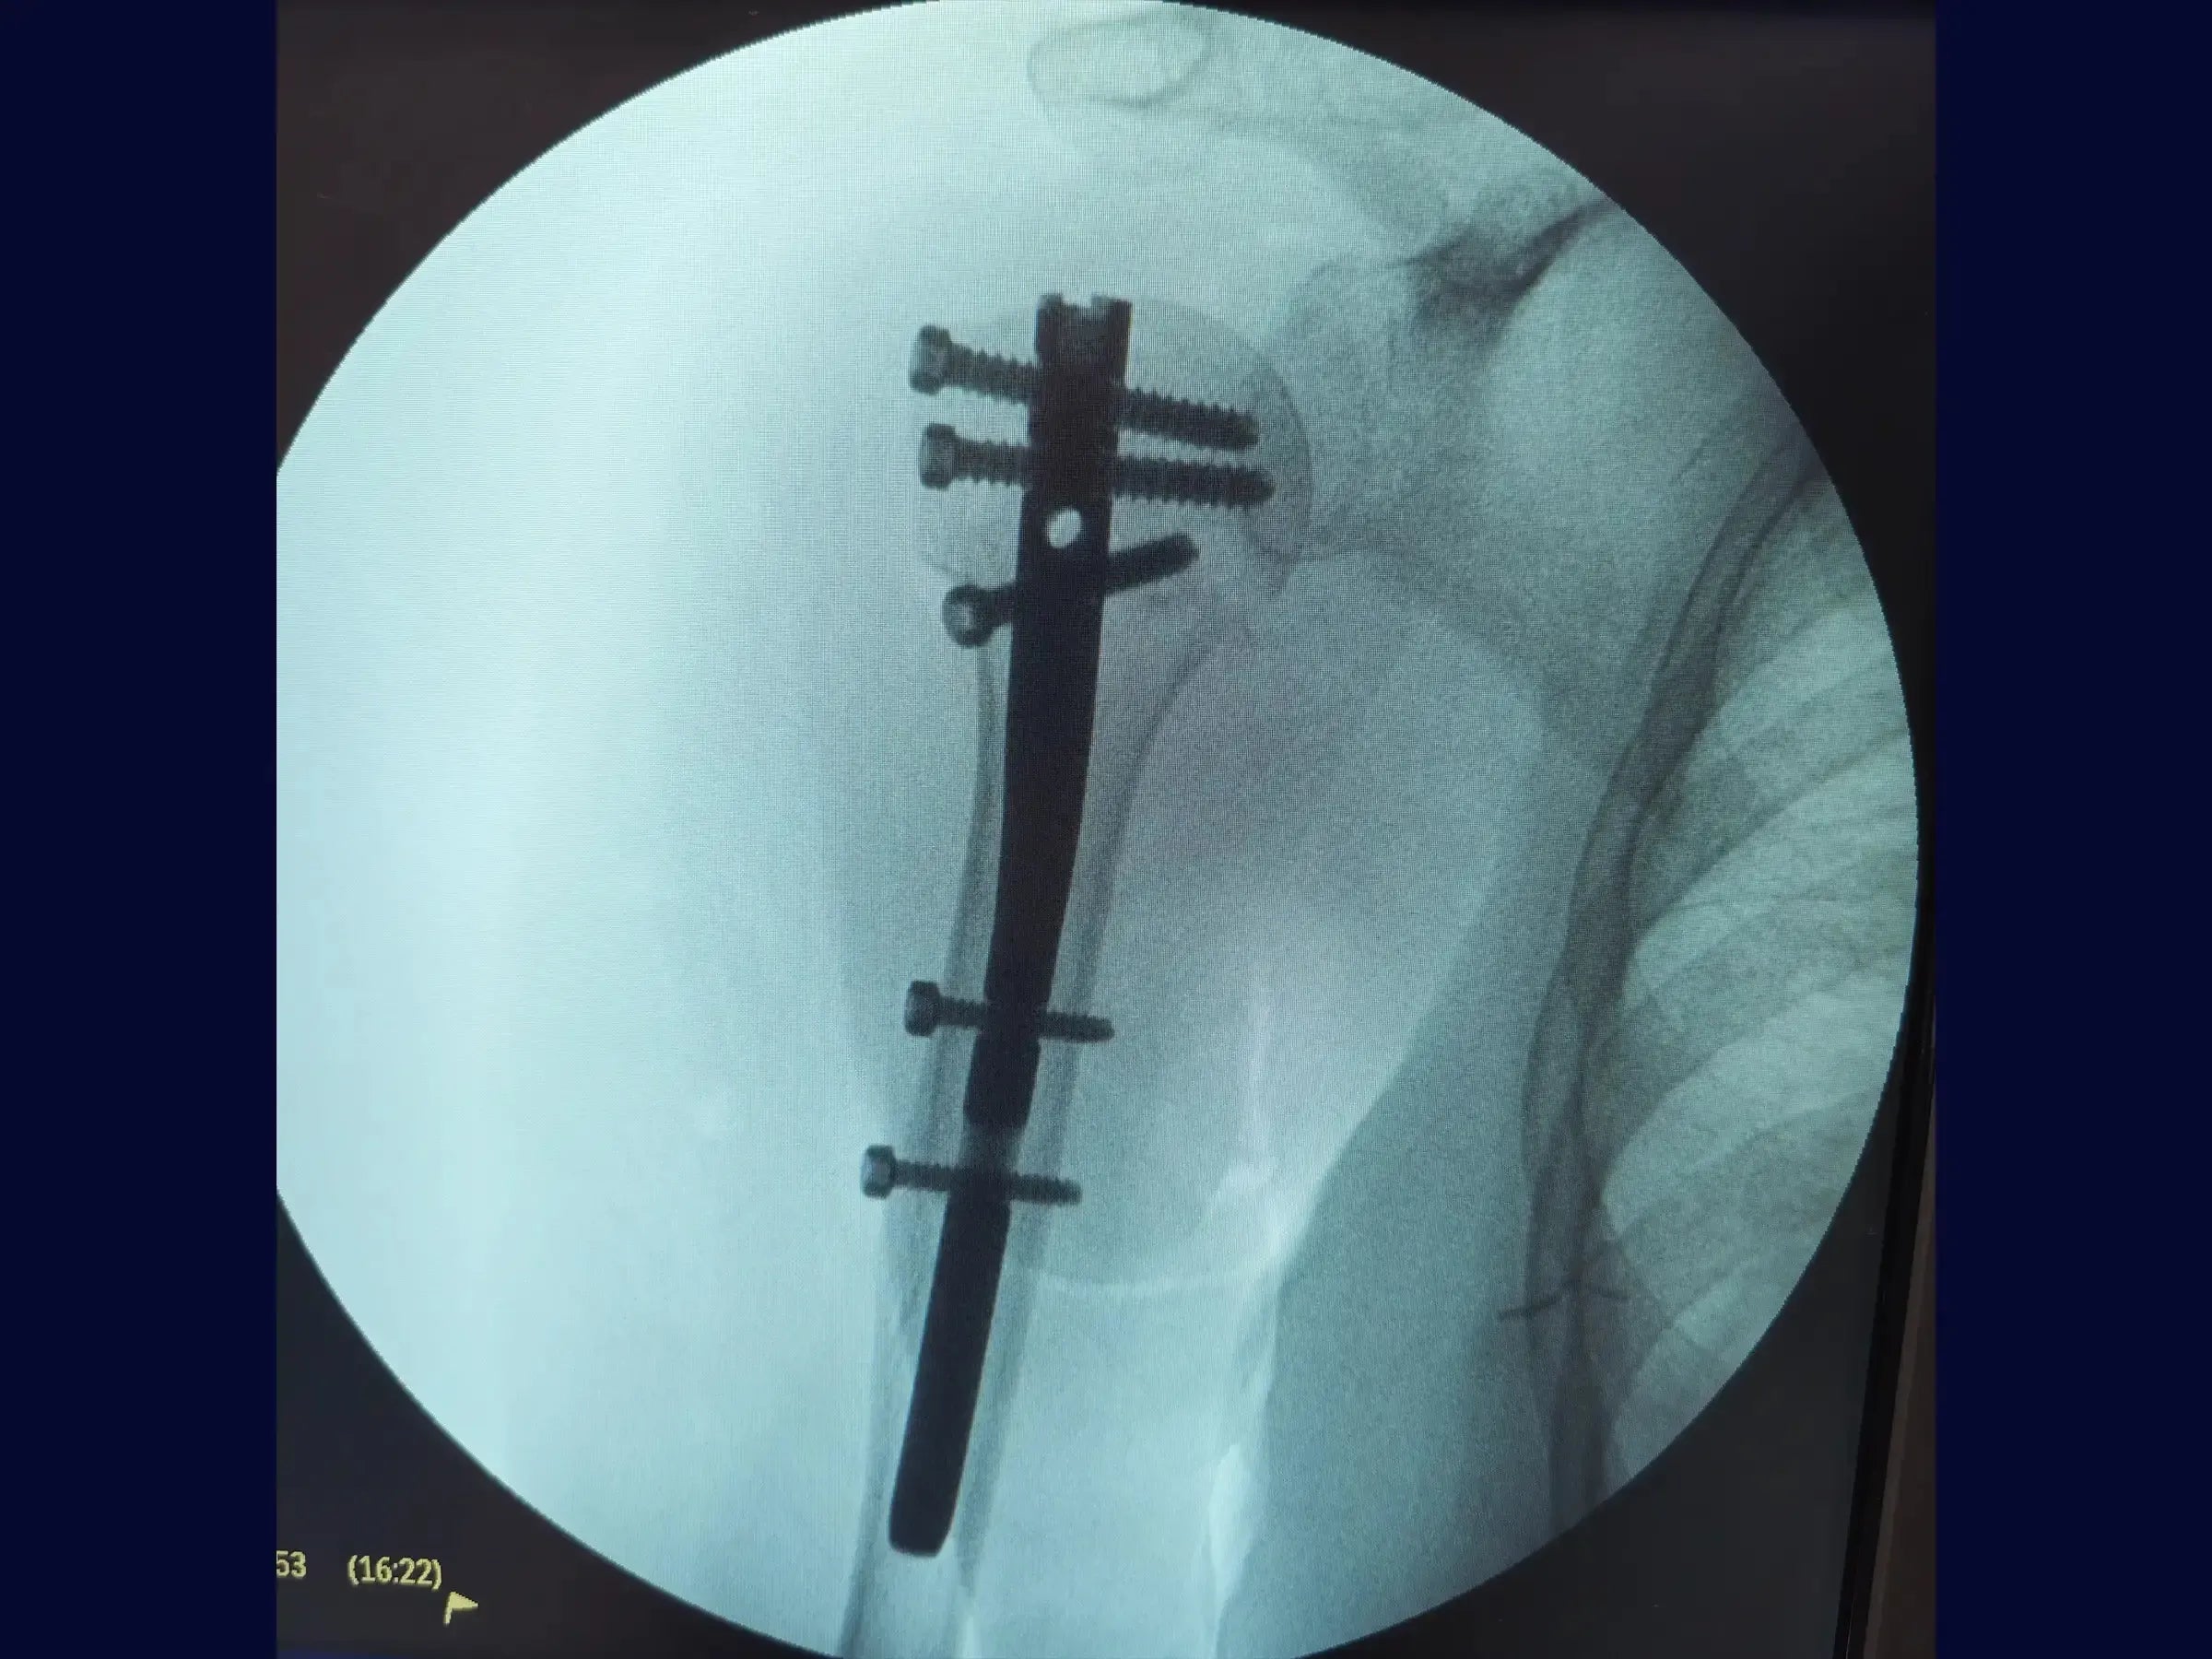

Haste Intramedular para Fratura do Úmero Proximal

A complexidade das fraturas do úmero proximal exige abordagens que preservem a função e minimizem a morbidade. Este treinamento oferece uma imersão técnica na osteossíntese com haste intramedular, utilizando acessos minimamente invasivos e uma técnica de manipulação do fragmento proximal com "joystick", focando na recuperação do eixo, rotação e versão da cabeça umeral sem a necessidade de uma redução anatômica precisa.

- Osteossíntese de fraturas do úmero proximal com haste intramedular.

- Fixação com parafusos de bloqueio proximal e distal.

- Fixação Estável com Parafusos de Bloqueio: Metodologia para inserção de parafusos de bloqueio proximais e distais através de mini acessos, incluindo a fixação do calcar, com foco na recuperação do eixo, rotação e versão da cabeça umeral.